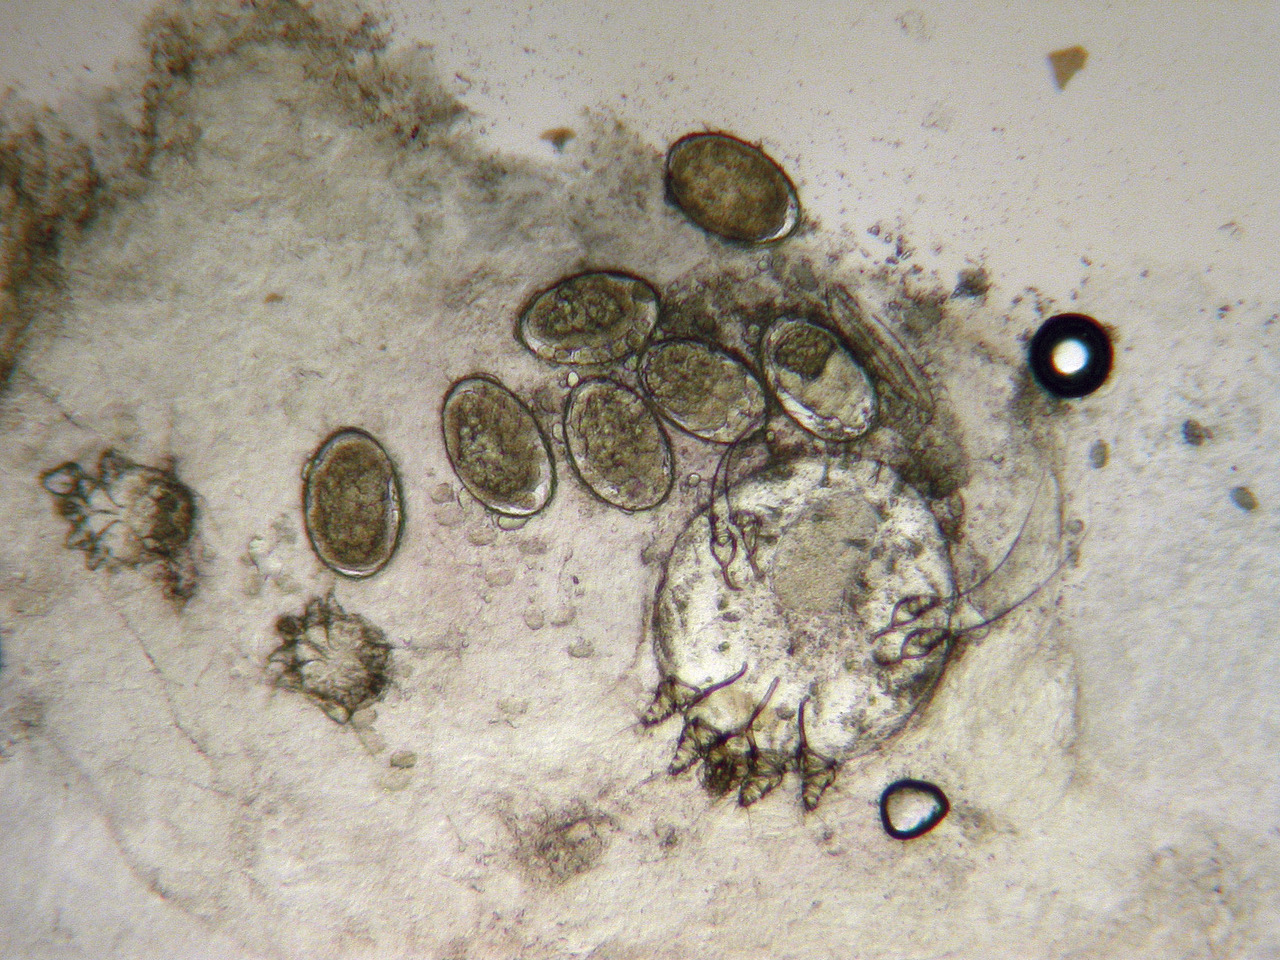

Dans les formes atypiques, des examens complémentaires parasitologiques peuvent venir étayer le diagnostic : grattage d’un sillon et recherche d’œufs, de larves, de scybales (excréments) ou de sarcoptes femelles adultes à l’examen microscopique direct (fig. 5 ), ou recherche d’un aspect caractéristique « en deltaplane » à l’aide d’un dermatoscope (fig. 6 ). La sensibilité de ces deux examens est globalement bonne et augmente avec la charge parasitaire et l’expérience de l’opérateur.

Dans les formes atypiques, des examens complémentaires parasitologiques peuvent venir étayer le diagnostic : grattage d’un sillon et recherche d’œufs, de larves, de scybales (excréments) ou de sarcoptes femelles adultes à l’examen microscopique direct (